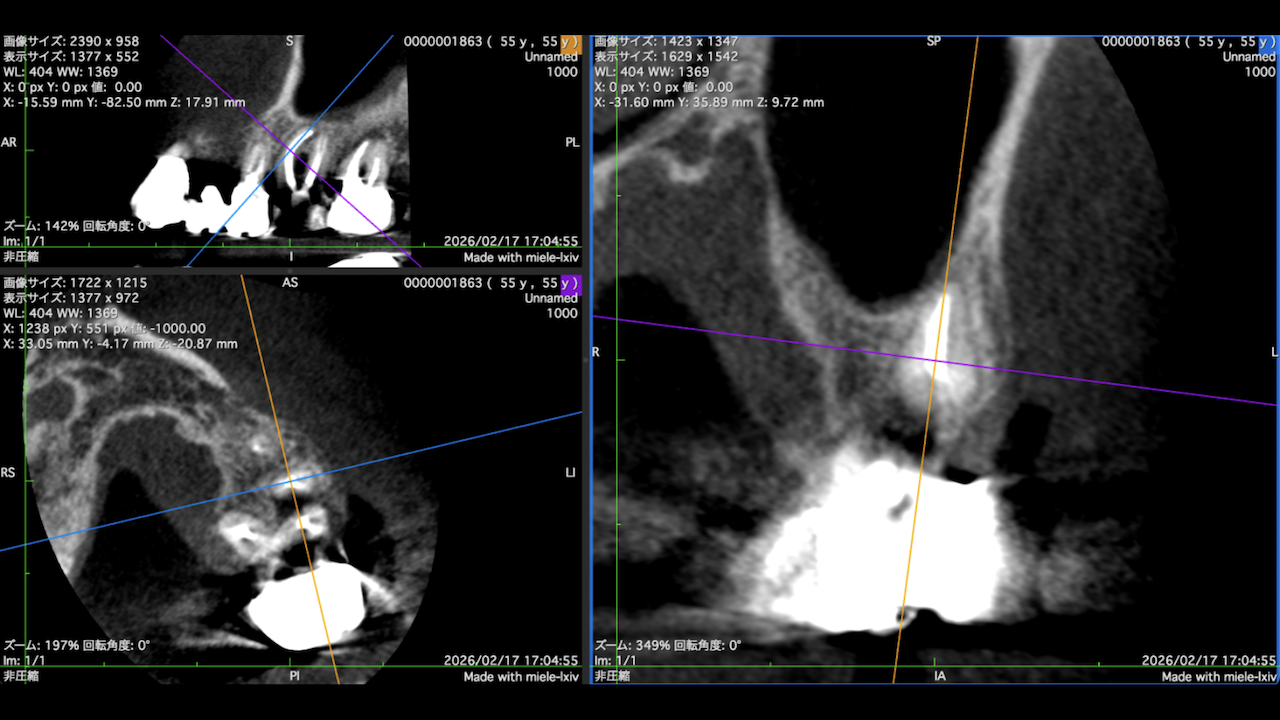

もう1ケースが以下だ。

#7がCold testに無反応である。

故に、#7,8の非外科的根管治療を行うことになった。

が、#8のメタルコアは外しにくいだろう。

CBCTでは2本とも口蓋側の皮質骨が消失している。

という絶望的な状況である。

ここから4ヶ月が経過すると…

臨床症状も皮質骨も大きく治癒している。

1年後の予後が気になるところであるが、すごくよくマネージメントできているだろう。